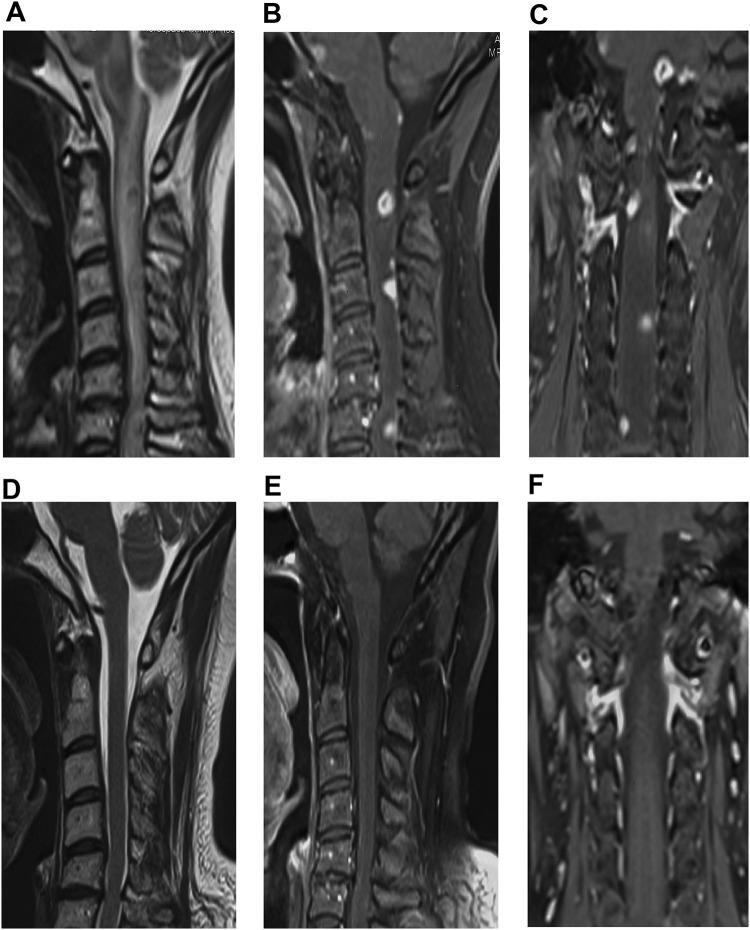

In the 397 neurosyphilis patients, seven had gumma - a frequency of 1.8%. Two of the seven (28.6%) were male. Their age ranged from 46 to 70 years, and the median symptom onset age was 56 years old. All patients experienced symptoms of unilateral limb weakness or numbness. Two patients displayed varying degrees of headache symptoms, three exhibited memory deterioration, and three manifested lightning pain. Enhanced MRI scans showed continuous nodule-like or partly high signal intensity of the brain or spine. The pathological sections of the intracranial syphilitic gumma displayed neuronal degeneration, proliferation of glial cells, and infiltration of lymphocytes. All serum samples showed decreased levels after therapy. The levels of WBCs and protein had reduced in all patients after therapy. All patients were followed up for 6 months to 1.5 years after therapy, and follow-up brain and enhanced spine MRI scans indicated part or complete remission after treatment.

在397例神经梅毒患者中,7例患有梅毒瘤,发生率为1.8%。7例中有2例(28.6%)为男性。他们的年龄在46至70岁之间,症状出现的中位年龄为56岁。所有患者均出现单侧肢体无力或麻木症状。2例患者表现出不同程度的头痛症状,3例出现记忆力减退,3例表现为闪电样疼痛。增强磁共振成像扫描显示大脑或脊柱有连续的结节样或部分高信号强度。颅内梅毒瘤的病理切片显示神经元变性、胶质细胞增生和淋巴细胞浸润。所有血清样本治疗后水平均下降。所有患者治疗后白细胞和蛋白质水平均降低。所有患者治疗后随访6个月至1.5年,随访时脑部和增强脊柱磁共振成像扫描显示治疗后部分或完全缓解。